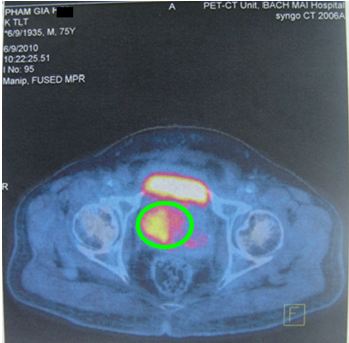

Bệnh nhân đã dược chụp PET/CT: Tuyến tiền liệt to, kích thước: 6 x 4,9 x 5,1 cm, nhu mô không đồng nhất, có nhiều nốt vôi hoá, thuỳ phải to hơn thuỳ trái, tăng hấp thu FDG không đồng đều, max SUV=4,98.

Hình 2: Hình ảnh PET/CT: tuyến tiền liệt (trong vòng tròn màu xanh) tăng hấp thu FDG không đồng đều, max SUV=4,98

Giá trị của PET/CT trong ung thư nói chung và ung thư tuyến tiền liệt nói riêng là chỉ trong một lần ghi hình (khoảng 30-45 phút, tùy bệnh); các bác sỹ có thể thu được cả hình ảnh CT bao gồm các thông tin chính xác về giải phẫu, vị trí cùng với hình ảnh chuyển hóa của PET cho ta thấy những thay đổi ở mức độ phân tử, tế bào ở giai đoạn rất sớm. Hệ thống máy máy PET/CT ở Trung tâm YHHN&UB bệnh viện Bạch Mai được trang bị đồng bộ, thống nhất nên hình ảnh PET/CT không chỉ sử dụng để chẩn đoán mà còn được sử dụng trực tiếp để lập kế hoạch xạ trị, định hướng cho vị trí sinh thiết.